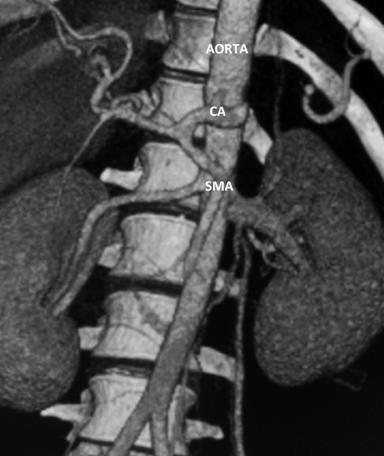

A 32 year old male patient diagnosed as alcohol related acute necrotising pancreatitis (ANP) 2 months ago, now presented with abdominal pain and early satiety. Contrast enhanced computerized tomography (CECT) showed 12 cm walled off pancreatic necrosis (WOPN) (Figure 1). Endoscopic ultrasound (EUS) revealed large WOPN and power doppler revealed vascularity in collection with pulsatile flow suggestive of blood leaking into collection (Figure 2). However, no abnormal vessel or pseudoaneurysm could be identified. CT angiography (CTA) also showed normal major abdominal arteries (Figure 3). Since patient was symptomatic, after informed consent EUS guided transmural drainage was attempted. Now there was no vascularity in collection and procedure was successfully accomplished. A 7 Fr nasocystic drain (NCD) was inserted and it drained purulent material. Patient had marked symptomatic relief but 6 hours later had severe pain and hematemesis with blood coming through NCD also. CTA revealed blood in WOPN but no abnormal bleeding vessel was identified (Figure 4). Digital subtraction angiography (DSA) also did not reveal any abnormal or bleeding vessel. The patient was managed with blood transfusion and NCD was kept patent by intermittent flushing. The bleeding subsided and the effluent from NCD cleared in 48 hours. The NCD was replaced with 10 Fr pigtail stents and CT abdomen done 3 weeks later revealed resolution of WOPN (Figure 5). The patient has been asymptomatic over a follow up period of 13 months.

Figure 3. CTA: normal major abdominal arteries (CTA: CT angiography; CA: Celiac axis; SMA: Superior Mesenteric Artery). |